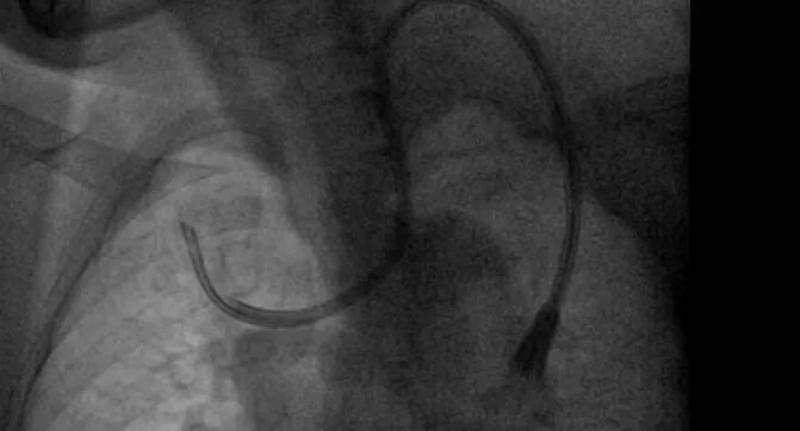

不久前,一位来自河源的患者到惠州市中心人民医院中文博彩平台分院(中文博彩平台人民医院)肾内科纠正导管位,这位日常是在当地的医院进行腹透导管,但总有不适感产生,听闻惠州市中心人民医院中文博彩平台分院(中文博彩平台人民医院)肾内科导管技术优秀,慕名场来求医。这位病人在当地医院进行血液透析,但导管流量不足,无法常见透析,到了惠州市中心人民医院中文博彩平台分院(中文博彩平台人民医院)就医以后,肾内科主任吴勇对他进行了全面的检查,发现该病人体内的导管已经像项链一般绕脖一圈,需要立马纠正。吴勇马上联系了惠州市中心人民医院的手足外科专家进行会诊,经讨论后对患者进行了球囊扩张术,并重新置入新的导管,术后患者透析顺利,返回当地后也能继续顺利透析。该病人对惠州市中心人民医院中文博彩平台分院(中文博彩平台人民医院)微创置管导管技术表示了高度的认可,并定期回院复诊。

肾内科从2018年分科建立以来,逐步发展壮大。在新一代学科带头人吴勇的带领下,学科克服了人才引留困难、临床科研基础薄弱、信息相对闭塞等难题,全科上下积极进取、砥砺前行,在诊疗技术水平、医疗服务能力、科研教学能力、人才培养及学科影响力等方面取得了重大突破。如前期需要在手术室剖腹进行的腹透置管手术,术后创口大,手术时间久等一系列缺陷,存在许多弊病,吴勇首先对其进行针对指导改良,微创化、轻量化,从经皮穿刺置管术转变到现在的改良型腹腔镜下腹透置管术,患者术后半日即可下床自行活动,不会有明显痛苦。科室还开展了上腔静脉狭窄球囊扩张术,解决血液透析长期导管带来的副作用。

2. 血管通路手术、DSA下的疑难置管,上腔静脉造影+球囊扩张+置管术(静脉置管、动静脉内瘘、血液透析长期静脉导管),彩超引导下经皮静脉球囊扩张术,是血液透析病人血管通路狭窄治疗的利器,可以减少病人痛苦,最大的可能保护病人的血管。